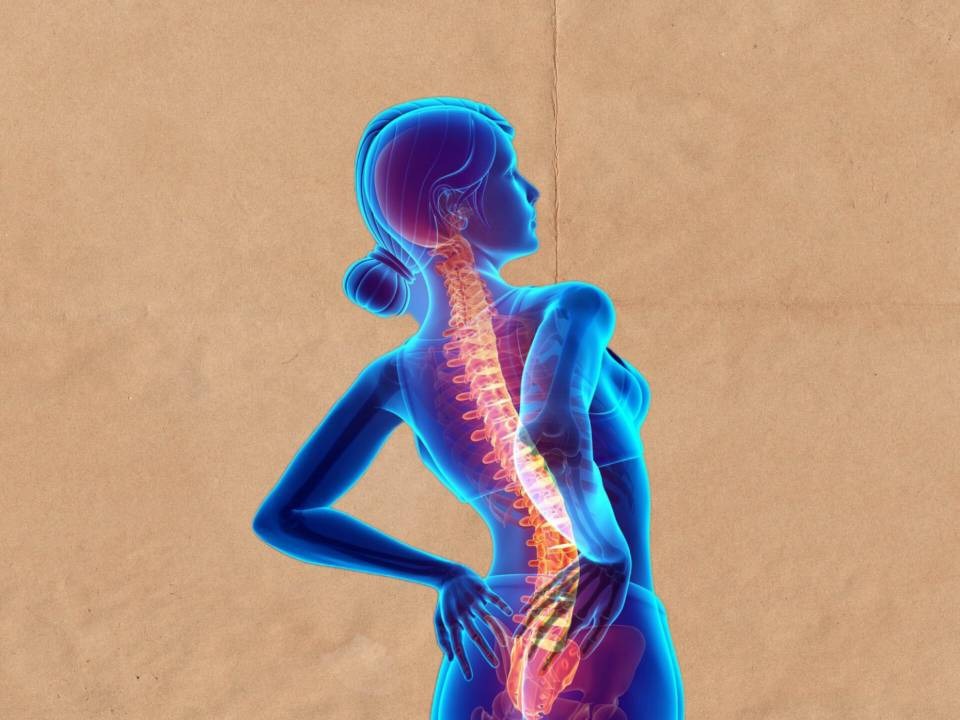

کمر درد

مشکل و شکایتی شایع. 80% افراد در زندگی خود به جهت آن به مراکز درمانی مراجعه می کنند. عوامل متفاوتی در کمر درد ها اثرگذارند به طوری که تشخیص را برای درمانگر می تواند دشوار کند. دانش فیزیوتراپی کمر درد ها را در 2 دسته حاد و مزمن می داند. کمر درد های حاد تا 90 روز می توانند به درازا بکشند. این در حالی است که کمر درد های مزمن درد می تواند بیشتر زمان ببرد.

ستون فقرات

شامل 33 مهره است: 7مهره گردنی، 12 مهره پشتی، 5 مهره کمری، 5 مهره خاجی و 4 مهره دنبالچه. هر مهره از 2 بخش ساخته می شود شامل جسم مهره و قوس مهره در پشت. جسم و قوس مهره ای به گونه به یک دیگر متصل می شوند به طوری سوراخ مهره ای را تولید می کنند. سوراخ های بین مهره ای در کنار یک دیگر قرار می گیرند و مجرای نخاعی را می سازند. طناب نخاعی در مجرای نخاعی قرار دارد. بین جسم هر دو مهره یک دیسک قرار می گیرد. دیسک های بین مهره ای فشار را از روی ستون فقرات برمی دارند.

ستون فقرات محور مرکزی بدن را تشکیل می دهد و در پشت تنه و در خط وسط قرار دارد.

علت های کمر درد

عوامل متفاوتی در کمر درد اثرگذارند. از مهم ترین عوامل کمر درد می توان به موارد زیر اشاره کرد:

1-بی تحرکی و سندرم بی تحرکی 2- درد ها و عوامل مکانیکی 3- درد التهابی 4- عفونت 5- تومور 6- عروق 7- روانی

90 % کمر درد ها منشا مکانیکی دارند. بیشتر این چالش ها نیز در بخش پایینی فقرات کمری است. (Lumbosacral) از مهم ترین علت های درد های مکانیکی می توان به این موارد اشاره کرد: 1- اسپاسم عضلانی 2- آسیب مفصلی 3- فتق دیسک 4- انحراف جانبی ستون فقرات 5- شکستگی ها 6- دررفتگی ها 7- کشیدگی عضلانی 8- پیچ خوردگی ها 9- آرتروز 10- تنگی کانال نخاعی 11- لغزش مهره ای 12- ناهنجاری های مادرزادی

تشخیص کمر درد

میانگین سنی افراد دچار کمر درد در سال های گذشته کم تر شده است. بخش بزرگ تر کمر درد ها ناشی از سبک زندگی نادرست است. هم چنین پایین بودن اطلاعات مردم در رفتار های نشستن، خوابیدن، جا به جایی اجسام و تغذیه نادرست است. در گذشته اغلب بیمارانی که از کمر درد شکایت می کردند میانسال بودند در حالی که زندگی امروزی جوانان را نیز به کمر دردی ها اضافه کرده است. در تشخیص کمر درد مهم ترین بخش معاینه فیزیکی و بالینی درمانگر است. در کنار آن مواردی دیگری از جمله رادیوگرافی، MRI، CT و آزمایش خون اشاره کرد.

درمان کمر درد

درمان فیزیوتراپی که بیشتر در ارتباط با درد های مکانیکی است. هم چنین درمان جراحی در آسیب های شدید. آموزش اصلاح پاسچر و فعالیت های روزمره.